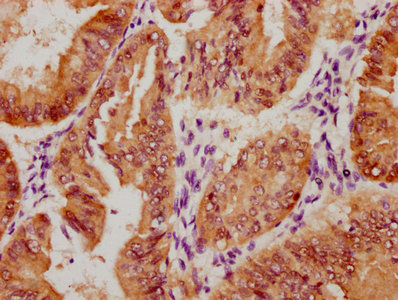

Immunohistochemistry of paraffin-embedded human lung tissue using CSB-PA064019ESR2HU at dilution of 1:100